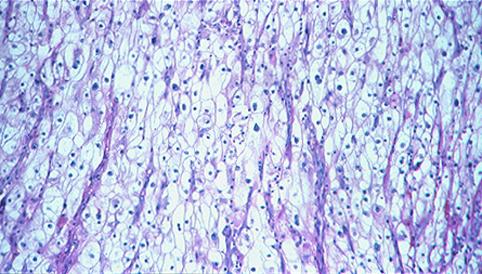

疾病(病理主体)的分类转移性肿瘤/

部位(按器官分)小肠/空肠

检查方法病理切片(微观)

肿瘤最大直径40以上